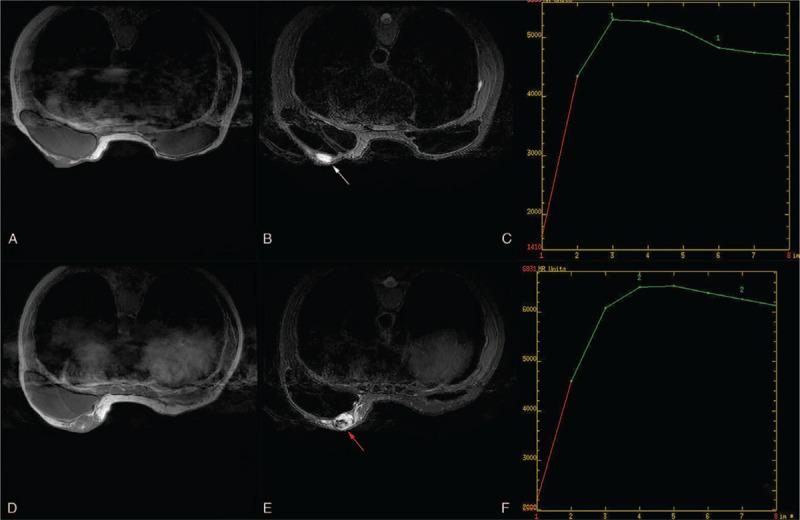

The tumor mimicked idiopathic granulomatous mastitis on magnetic resonance imaging (MRI) at the first presentation. Contrast-enhanced ultrasound (CEUS) was performed for further lesion characterization and showed heterogeneous rapid hyper enhanced. An ultrasound-guided core needle biopsy was performed, and the pathology report indicated a breast angiosarcoma.

After 8 months later, the tumor recurred, CEUS and MRI examination suggested PBA recurrence, then re-excision with implant removal was performed, the patient had a lung metastasis 4 months later eventually died 22 months after diagnosis.

It is not easy to diagnose PBA with the radiographic examination. This case's importance is by combining CEUS and MRI to reflect enhanced morphology and hemodynamic characteristics of PBA and help diagnose breast angiosarcomas.

肿瘤在初次就诊时的磁共振成像(MRI)上模拟特发性肉芽肿性乳腺炎。为进一步明确病变特征,进行了对比增强超声(CEUS)检查,显示不均匀快速高增强。进行了超声引导下的核心针活检,病理报告提示乳腺血管肉瘤。

8 个月后,肿瘤复发,CEUS 和 MRI 检查提示 PBA 复发,随后进行了再次切除和植入物取出,4 个月后患者出现肺转移,最终在诊断后 22 个月死亡。

影像学检查诊断 PBA 并不容易。这个病例的重要性在于结合 CEUS 和 MRI 反映 PBA 的增强形态和血流动力学特征,有助于诊断乳腺血管肉瘤。